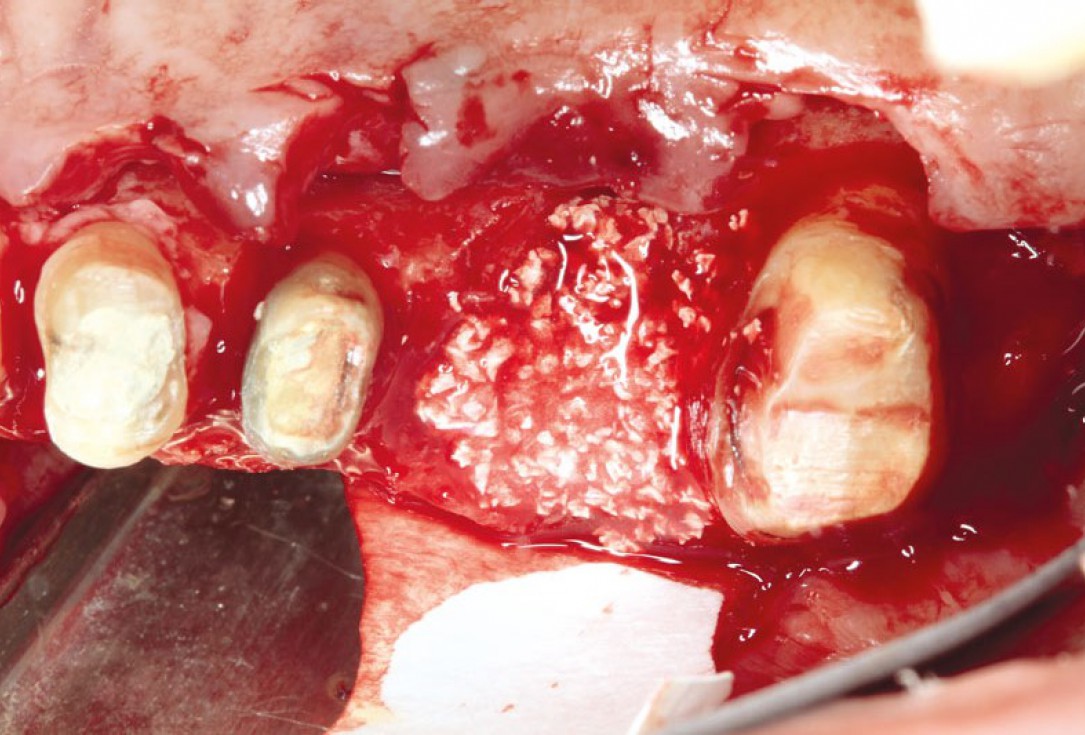

botiss cerabone® & Jason® membrane for block augmentation with autologous bone blocks - clinical case by Dr. S. Stavar

Initial clinical situation with single tooth gap in regio 21